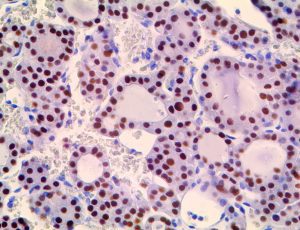

It is the ICU physician who is most likely to witness one of the deadliest manifestations of the abnormal immunological response, the cytokine storm syndrome (CSS). This response is also referred to by some as the cytokine release syndrome (CRS). CSS is characterized by continuous activation and expansion of macrophage and lymphocyte populations, which secrete large amounts of cytokines, causing the cytokine storm. This massive cytokine release is akin to hemophagocytic lymphohistiocytosis (HLH) disease, a syndrome characterized by initial unchecked and persistent activation of cytotoxic T lymphocytes and NK cells.

Clinical and laboratory manifestations of HLH include fever, enlarged liver and/or spleen, neurologic dysfunction, coagulopathy, liver dysfunction, cytopenias (i.e., low levels of erythrocytes, leukocytes, and/or platelets), hypertriglyceridemia, hyperferritinemia, hemophagocytosis, and eventually diminished NK cell activity as the immune system becomes progressively paralyzed. HLH can be familial (primary HLH) or secondary to another disease process (sHLH), such as rheumatic disease, in which it is referred to as macrophage activation syndrome (MAS, characterized by elevated ferritin).